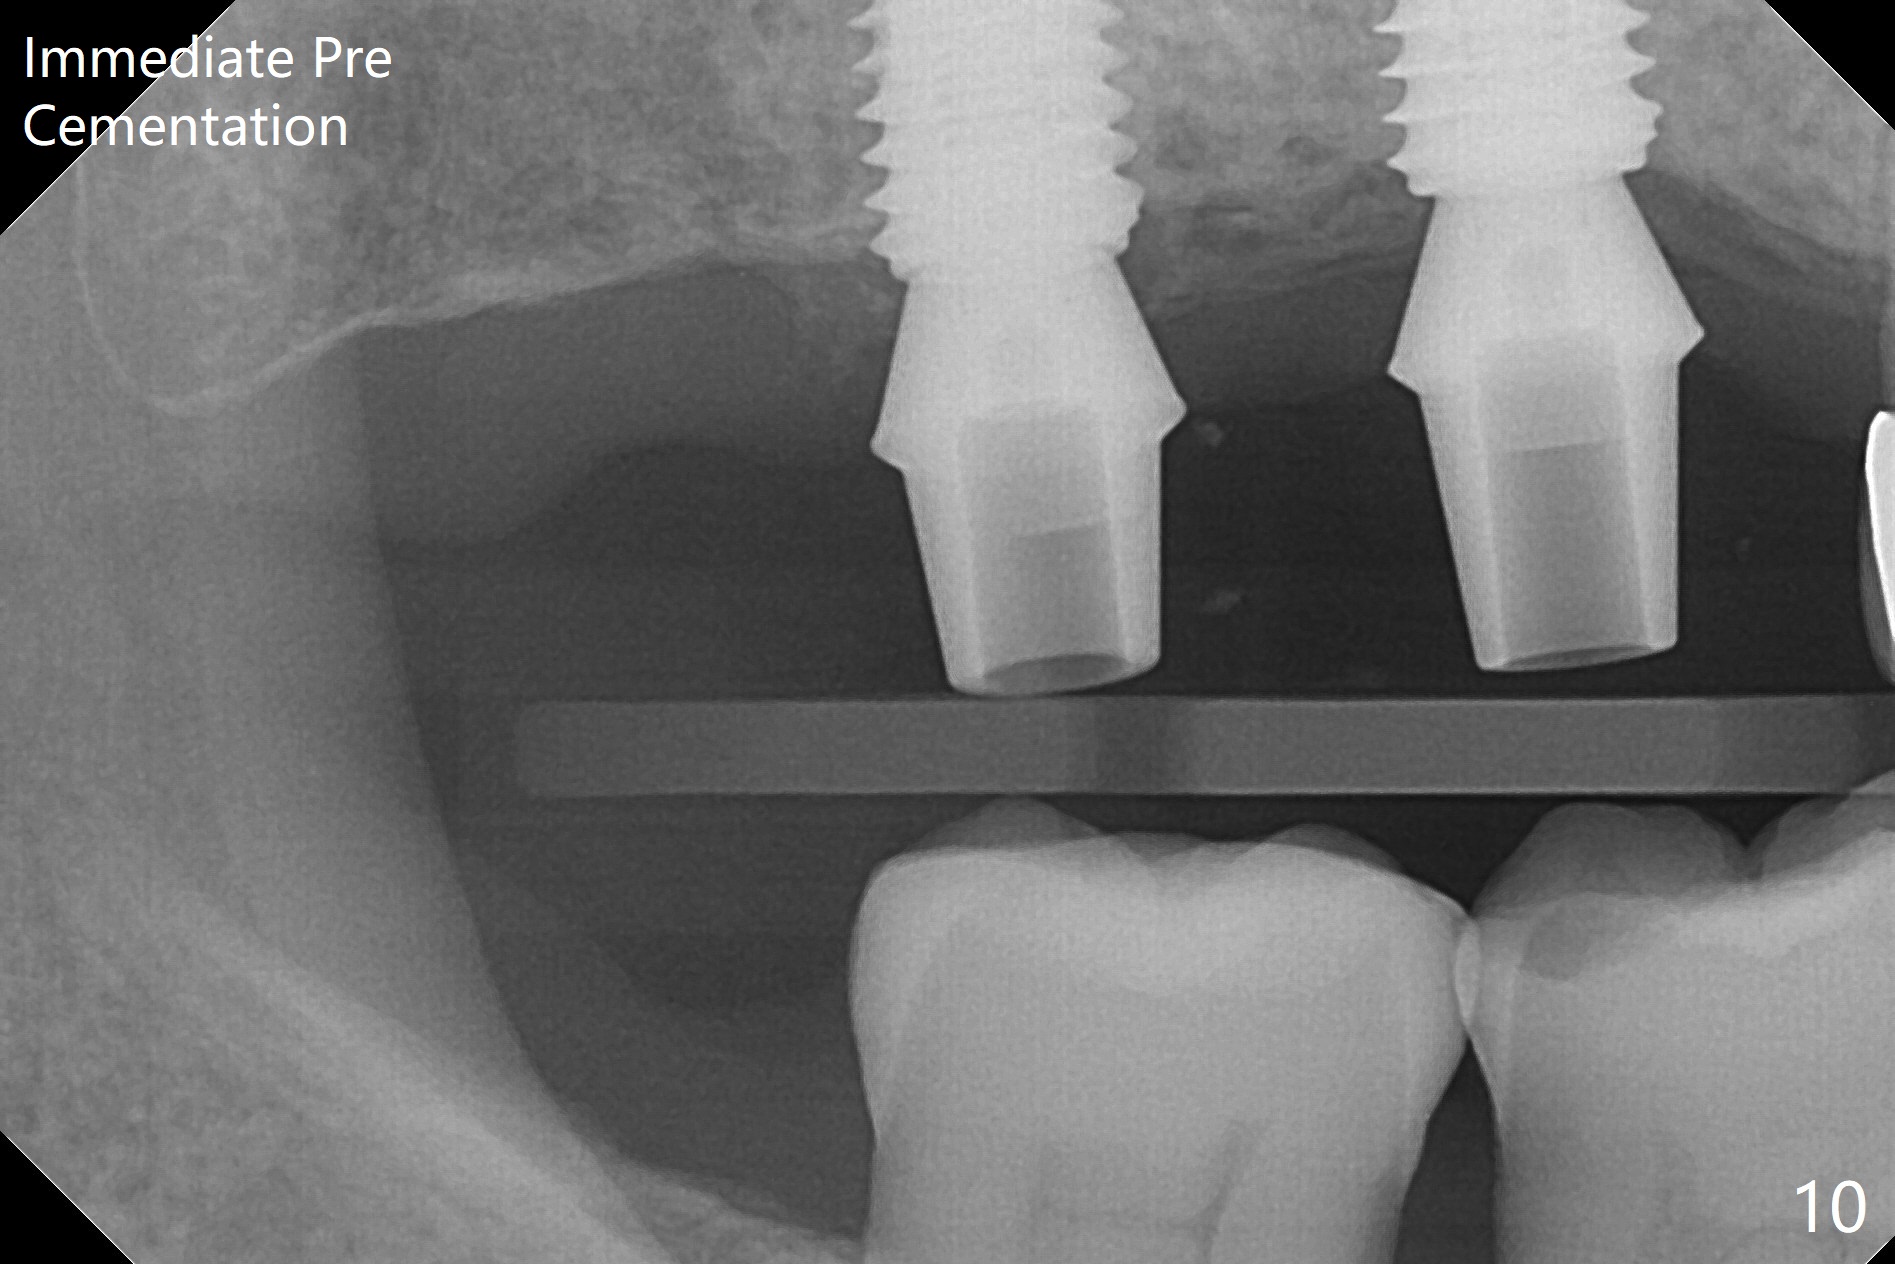

Two of 5x8.5 mm implants are placed at #2 and 3 with sinus lift using water ballooning technique; to avoid invading the neighboring root tips, an intraop PA is taken with a 2.2x11.5 mm drill at #5 (Fig.1). When a 2.5x11.5 mm 1-piece implant is placed at #7, there is 2.4 mm clearance from the impacted tooth (Fig.2). Following 1 mm deeper placement of the 1-piece implant, CT is taken to make sure that the threads are completely covered palatally (Fig.5 P). Interesting is that the sinus membrane is thickened at #2 and 3 (Fig.3 M), as compared to the clear sinus before surgery (Fig.3'). Bone graft is limited in the sinus (Fig.3 arrowheads). The implant at #5 (3.5x11.5 mm) is precisely placed subcrest bucco(B)-palatally (Fig.4). Since the limited field viewed CT does not cover the implant at #2 (Fig.3), immediate postop PA is taken (Fig.6). In fact all of the implants are placed subcrestal, as shown by intraoral X-ray 4 months postop (Fig.7-9). The abutments at #2, 3 and 5 are retorqued (30 Ncm) after crowns' try in and adjustment (Fig.10,11). There is a vertical gap between the implant and abutment at #2 (Fig.11 ^) and a horizontal one at #5 (<). There is apparently no bone loss 1 year 5 months post cementation (Fig.12).